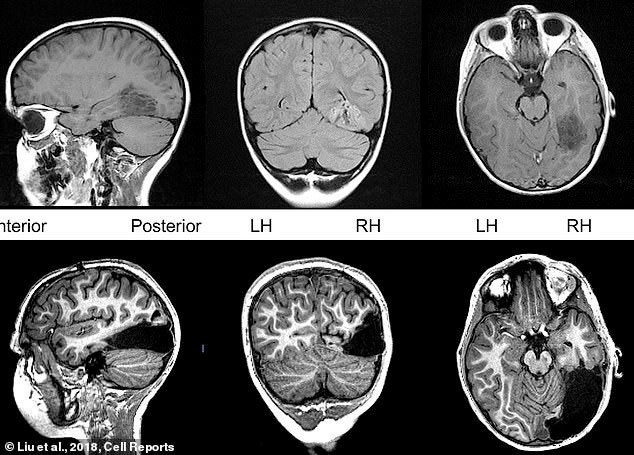

Tanner bị cắt bỏ 1/6 não bộ để ngăn ngừa chứng động kinh. (Ảnh: Dailymail).

Theo Daily Mail, 5 năm trước, các bác sĩ đã phải mở hộp sọ của Tanner, cẩn thận cắt bỏ một khối u lành tính có kích thước bằng quả bóng golf đang phát triển về phía sau đầu, chèn ép vào não. Nó gây ra chứng đau nửa đầu và co giật không thể ngừng ở cậu bé. Tuy nhiên, không một loại thuốc nào có thể chữa cho Tanner.

Phẫu thuật có thể ngăn chặn các cơn động kinh, nhưng nó sẽ phải loại bỏ một phần não bộ chịu trách nhiệm nhìn và xử lý thông tin hình ảnh. Các bác sĩ phải loại bỏ tất cả thùy chẩm phải, một nửa thùy chẩm phần hướng về phía sau, sát cổ.

Nhưng hiện tại, dù bị mất 15% bộ não, phần não bên trái của Tanner đã đảm nhận nhiệm vụ mà phần bên phải bị mất đã làm. Hiệu ứng này giúp cậu bé nhận diện được khuôn mặt và vật thể ở phía bên trái tầm nhìn.

Kể từ khi Tanner tỉnh dậy sau phẫu thuật, các bác sĩ đã theo dõi chặt chẽ cậu bé với sự hỗ trợ của máy cộng hưởng từ chức năng fMRI. Trong vòng 3 năm, Tanner cũng thường được cho làm các bài kiểm tra thị giác và hành vi, để so sánh với những đứa trẻ khỏe mạnh khác ở cùng độ tuổi. Cậu bé có chỉ số IQ trung bình, kỹ năng nhận thức ngôn ngữ và thị giác của cậu phù hợp với lứa tuổi.